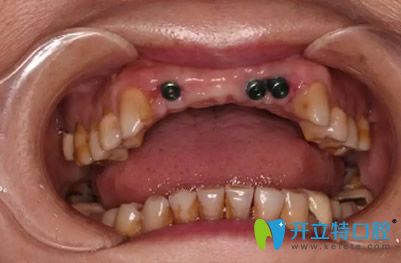

植入種植體3個(gè)月后,檢查結(jié)果顯示,種植體與牙槽骨結(jié)合情況非常好,完全達(dá)到二期修復(fù)標(biāo)準(zhǔn)。為了實(shí)現(xiàn)好的美觀效果,孔醫(yī)生結(jié)合經(jīng)典的紅白美學(xué)標(biāo)準(zhǔn),按照牙齦、牙齒與面部的黃金比例,為路女士量身定制5顆全瓷修復(fù)體。